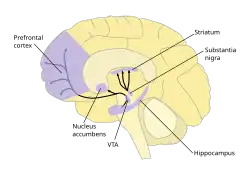

A dopamina (DA, uma contração de 3,4-di-hidroxifenetilamina) é um neurotransmissor monoaminérgico, da família das catecolaminas e das feniletilaminas que desempenha vários papéis importantes no cérebro e no organismo. Os receptores de dopamina são subdivididos em [[Receptor D1 de dopamina|D1], D22, D3, D4 e D5, de acordo com localização no cérebro e função. O cérebro contém várias vias dopaminérgicas, como a via mesolímbica, que desempenha um papel importante no sistema de comportamento motivado a recompensa.[3] [4] A maioria das recompensas aumentam o nível de dopamina no cérebro, e muitas drogas viciantes aumentam a atividade neuronal da dopamina. A dopamina é produzida especialmente pela substância negra e na área tegmental ventral (ATV). A dopamina também está envolvida no controle de movimentos, aprendizado, humor, emoções, cognição e memória.[5]

A desregulação da dopamina está relacionada a transtornos neuropsiquiátricos como doença de Parkinson, no qual ocorre escassez na via dopaminérgica nigro-estriatal[7] , e na esquizofrenia, no qual ocorre excesso de dopamina na via dopaminérgica no mesolímbico e escassez na via mesocortical.[8]

Vias dopaminérgicas

- Via mesolímbica: sabe-se que a dopamina está relacionada ao pensamento. Esquizofrenia envolve aumento da atividade dopaminérgica nessa via.

- Via nigro-estriatal: a dopamina estabiliza os movimentos. A doença de Parkinson está relacionado a escassez dopaminérgica nessa via.

- Via túberoInfundibular: a dopamina na hipófise inibe a prolactina. Na Depressão pós-parto ocorre diminuição da dopamina.

- Via mesocortical: a Dopamina atua no controle do apetite.